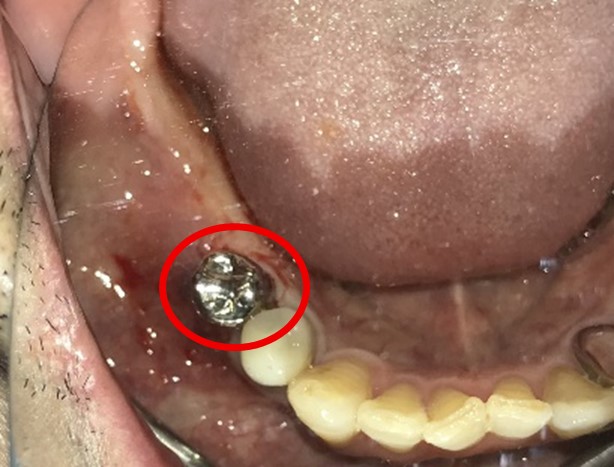

右下の奥歯の歯肉が痛い。時々血が出たり、腫れたりする。

治療内容

右下のブリッジの支台になっている前方の歯が、歯根破折を起こしていましたので抜歯しました。インプラントを右下第一、第二大臼歯部に2本埋入しました。

所感

実はこの患者さんは、2014年に右下の第二大臼歯(一番奥の歯から2番目の歯)を歯根破折により抜歯し、その際の治療法としてブリッジを選択されました。そして今回、ブリッジを支えていた歯(第一大臼歯)がついに歯根破折を起こしてしまいました。

ブリッジは、3本分の歯を2本の歯で支えるため、支える歯の負担が大きくなり、歯根破折を起こす危険性が高くなります。

今回の抜歯後は、歯が2本ない状態になるので、そこを補う方法についてご説明しました。選択肢は再度ブリッジを入れるか、インプラントになります。ブリッジにして支える歯がまた折れてしまうと歯が3本ない状態になる可能性があるため、インプラントを選択されました。もし11年前にブリッジではなくインプラントを選んでおられたら、今回の歯根破折や抜歯は起きなかったかもしれません。ブリッジは、噛む力の強い方、歯ぎしりをする方、硬い食べ物が好きな方は、支えの歯の負担がより大きくなるのでおすすめできません。

インプラントは、それ自身が単独で植立しているので、他の歯に負担がかかりません。インプラントは、欠損を補う最良の方法と考えます。

インプラント2本:¥726,000(税込)

Before

抜いた歯 真二つにわれています

After